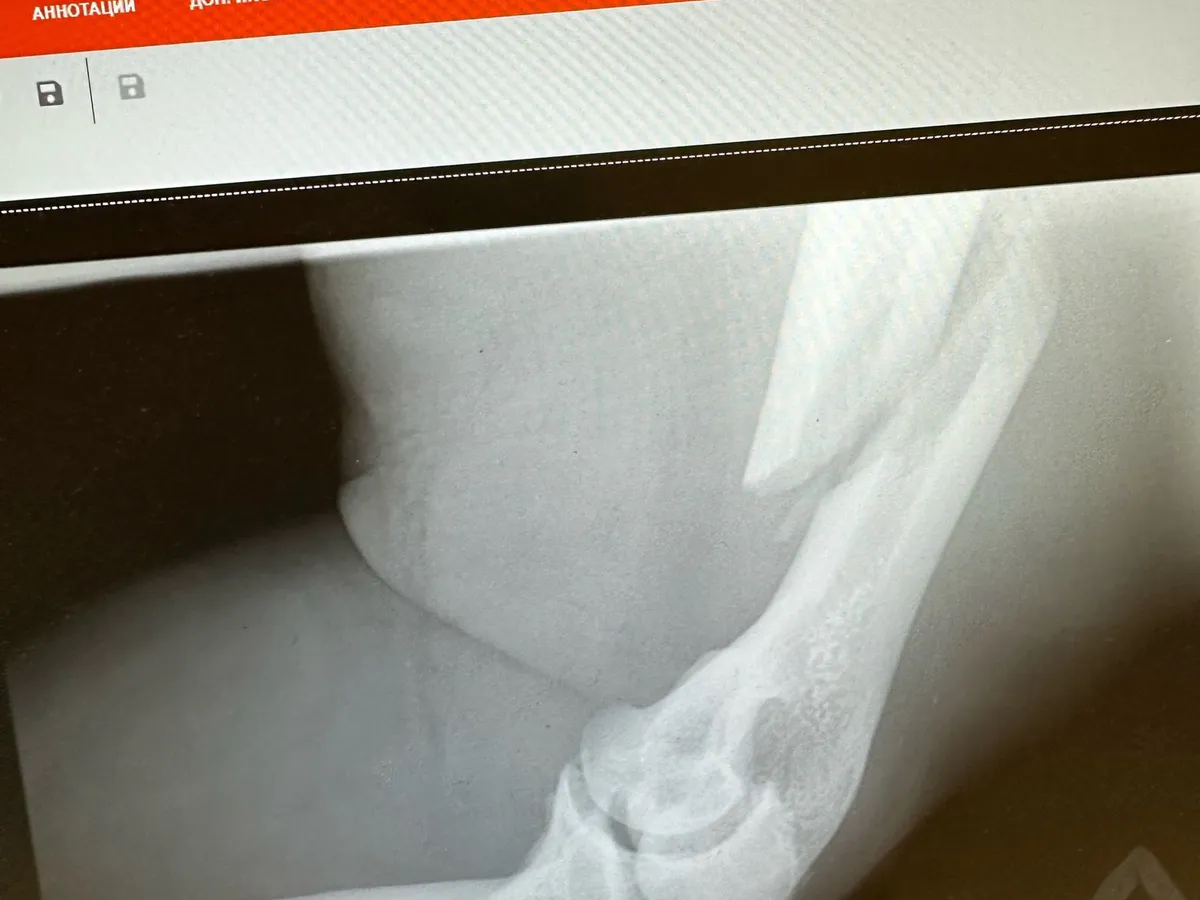

Рязанский армрестлер Андрей Попов пережил тяжелую травму во время спортивных состязаний и был прооперирован. Подробности сообщили в телеграм-канале Iron News. Уточняется, что Попов получил винтовой перелом плечевой кости и отрыв бицепса в ходе армфайта со спортсменом Дмитрием Голубочкиным.

Операция заняла порядка трех часов, оказалась достаточно сложной и требовала специального подхода. В результате усилиями специалистов установлена пластина для стабилизации сломанной кости.